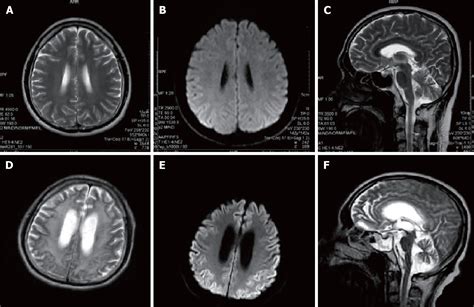

• Imaging Studies: Magnetic Resonance Imaging (MRI) and other imaging techniques can reveal characteristic changes in the brain, such as atrophy and the presence of amyloid plaques.